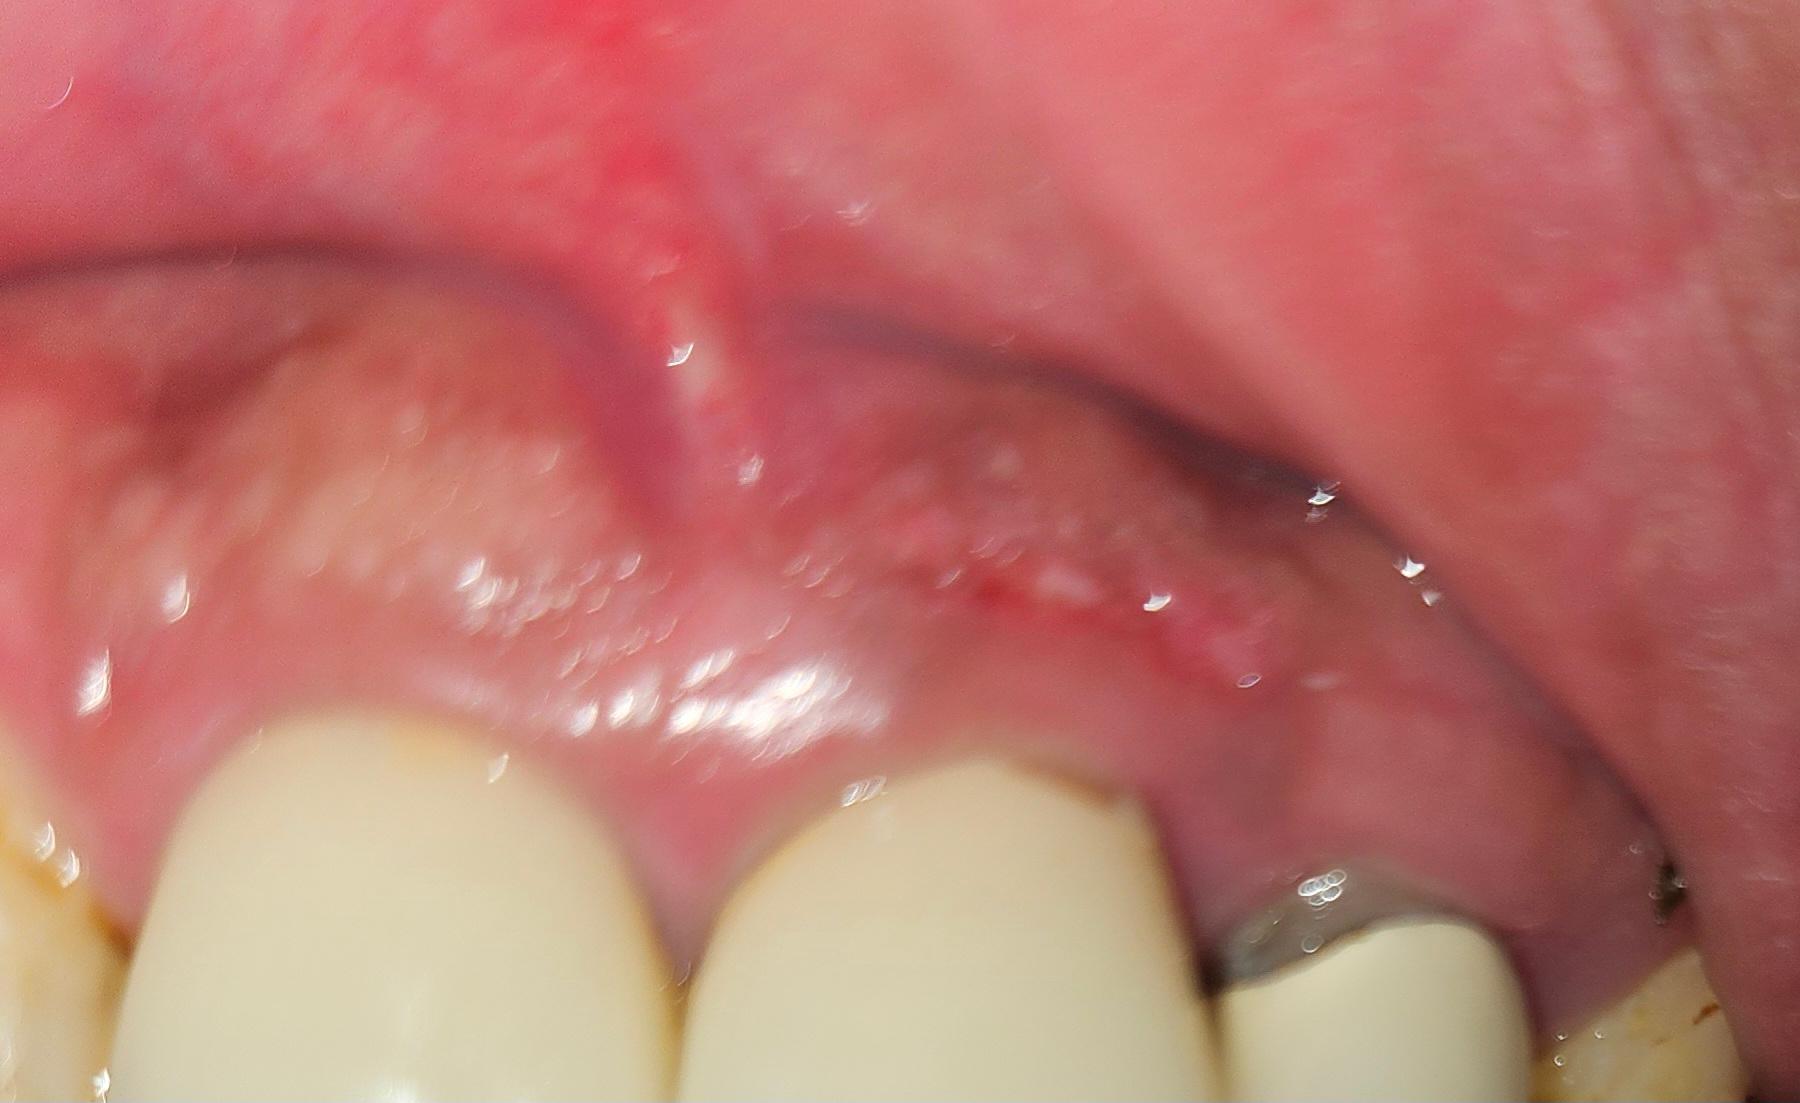

잇몸에 이상한게 생겼어요 어떤지 봐주세요

잇몸에 몇개월전부터 나더니 옆으로 번지고 있어요 이게 뭘까요? 통증은없고 약간 흑색으로 변하는곳도있고.. 병원가니까 염증이나 바이러스는 아닐 것 같다고 해요 암일 가능성도 있나요?

해당 소견은 이비인후과 보다는 치과 진료가 필요합니다.사진 기준으로 보수적으로 판단드리면, 전형적인 급성 염증 소견은 아니지만 다음 세 가지 범주로 감별합니다.

1. 색소 침착(멜라닌 침착, 금속성 착색 등)

여러 달에 걸쳐 서서히 넓어지고 통증이 없다는 점, 표면이 비교적 매끈하다는 점이 색소성 변화와 맞습니다. 치과 치료 후 금속 재료 주변에 국소 착색이 생기는 경우도 있습니다.

2. 만성 자극에 의한 증식(섬유종·증식성 병변)

치실 습관, 강한 양치, 보철물 경계 등으로 특정 부위가 반복 자극되면 통증 없이 서서히 커지는 잇몸 증식이 생길 수 있습니다.

3. 악성 가능성(드묾)

잇몸암은 보통, 불규칙한 형태, 딱딱한 결절, 쉽게 피남, 궤양·통증, 빠른 크기 증가가 동반되는 경우가 많습니다.

현재 사진처럼 경계가 비교적 매끈하고 색 변화만 있는 형태는 전형적 양상은 아닙니다. 다만 몇 개월 이상 지속·확장되는 병변은 조직검사 없이 단정하기 어렵습니다.

■ 필요한 확인

치과 구강내과 or 구강악안면외과에서 확대검진, 임상사진 비교, 필요 시 간단한 조직검사 정도면 진단이 명확해집니다. 조직검사는 통증이 거의 없고 5분 내외로 끝나는 간단한 시술입니다.

현재로서는 악성 의심 소견은 낮아 보이나, 수개월 지속·확대라는 점 때문에 최소 한 번은 전문 진단을 권합니다.